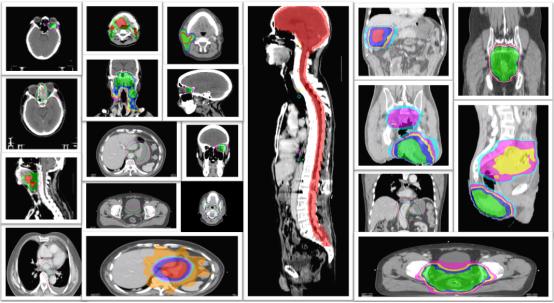

图1多种肿瘤患者放疗剂量分布图